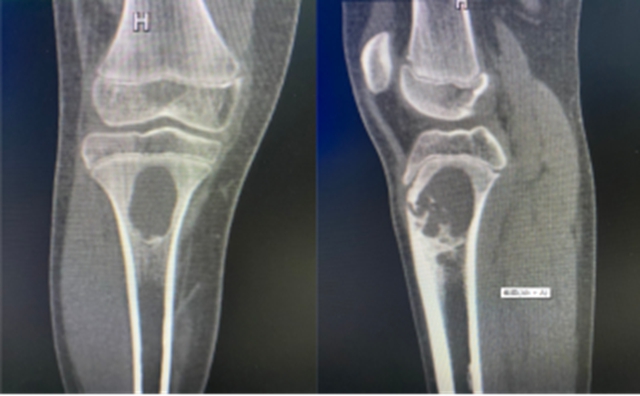

影像检查提示:小王胫骨近段偏心性皮质骨内出现了溶骨病变(骨化性纤维瘤),没想到病根竟是让人意想不到的肿瘤。

8月3日,在李森教授的指导下,由骨伤科脊柱·肿瘤一组朱凯主治医师、雷杨医师为小王完成了胫骨近端病灶清除、植骨、肢体重建手术治疗,将肿瘤彻底清除、灭活,重建原有肢体骨骼形态,手术历时2个半小时,顺利完成。